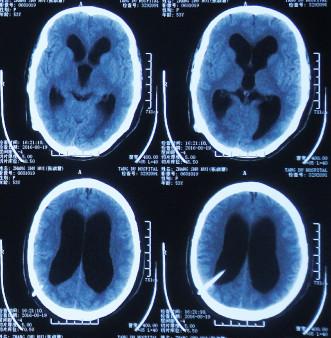

第2次出院后4月余即2016年6月7日,因第3次“发热”就诊当地某医院中医门诊,经中医治疗近两月时间。于2016年6月21日复查头颅CT:幕上脑室仍扩张(图-7)。治疗期间发热曾缓解,但之后发热仍反复。

图-7:2016年6月21日头颅CT

住院后3天即2016年8月19日,查头颅CT:幕上脑室扩张(图-9)。

图-9:2016年8月19日头颅CT

第3次出院后21天即2016年9月23日,复查头颅CT:幕上脑室仍扩张(图-10)。

图-10:2016年9月23日头颅CT